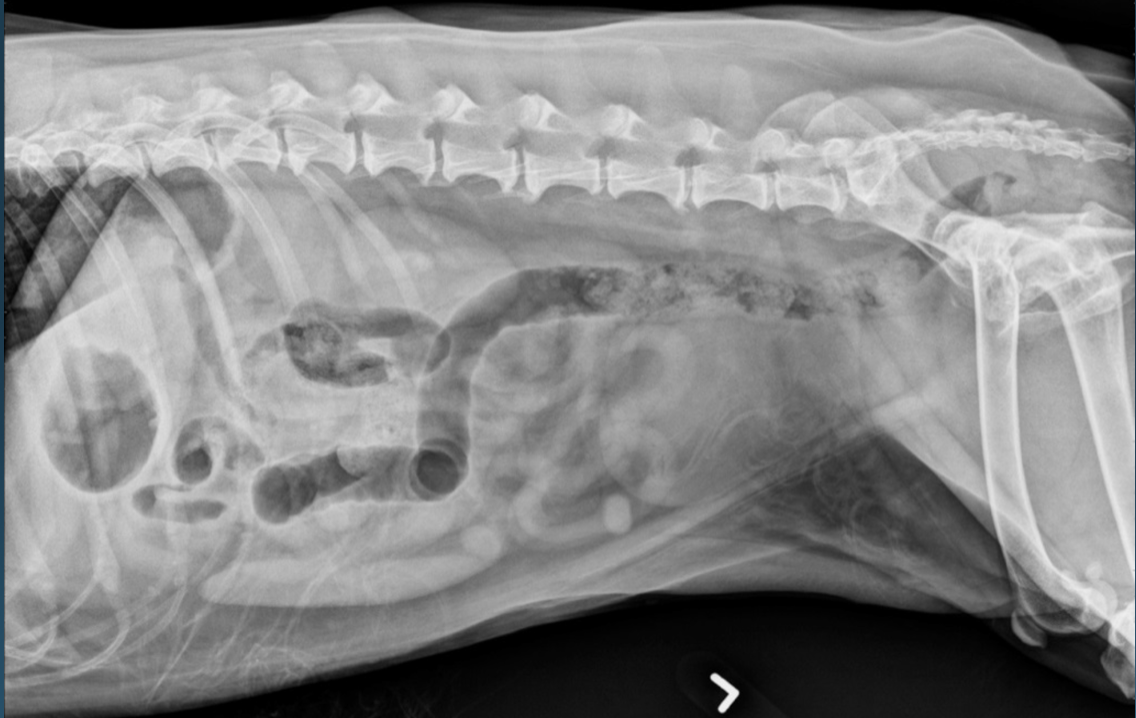

What is shown in these images?

normal abdomen and normal body wall in a dog